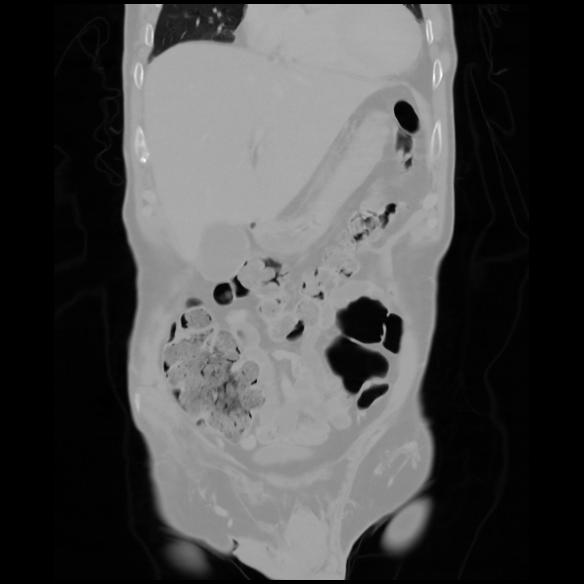

6 CUERPO,CE,Coronal,3.000,CUERPO,Coronal,